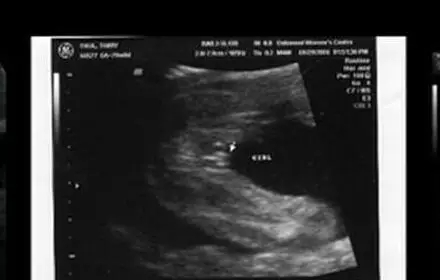

三、国外新奇小肿块原理

个别有经验的妈妈还有另一种看图方式:十一至十三周,所有的胎儿都会在双腿之间长出一个小肿块,而这个肿块的角度则会显示出它是个男孩还是女孩。据说如果小肿块翘起来30度以上就是男孩,但如果小角度就是女孩。请看下面的例子。

2017生男生女计算器

小肿块没有指向三十度以上 - 事实上它几乎是水平的!